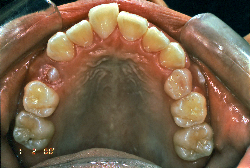

初診時の状態ですが、前歯の噛み合わせが逆転していて、下の前歯が外側に来て、上の前歯が裏側になっています。口元の様子ですが、前歯の重なり方が逆なので、唇の様子もそれを反映して、下唇が突出しています。反対咬合としてはかなり重症です。

分析してみると歯の傾き方に問題があるだけでなく、顎の骨の大きさと形にも問題があることが分かりました。ただし、骨の問題点が見つかったからと言って、必ずしも外科矯正になるわけではなく、このくらいの症状ですと、通常の矯正でもきれいに治すことができます。

診断の結果、下の前歯を正しい位置まで内側に入れていくためには、十分な隙間を確保することが避けられないと判断し、上の左右第二小臼歯と下の左右第一小臼歯は抜歯させて頂くことにしました。歯の本数は減りましたが、歯科医学的評価も大きく改善しましたし、審美的にも大幅な改善が見られますね。特に口元の様子が全然変わりました。